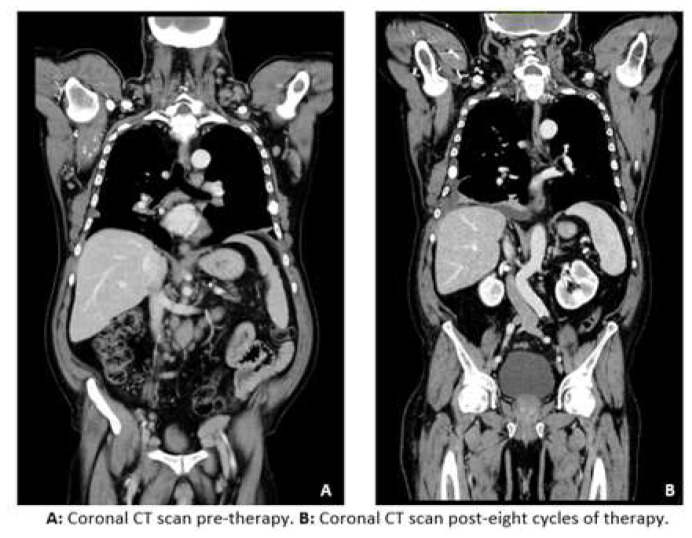

A Case of Multiple Myeloma in a Patient in Treatment for Chronic Lymphocytic Leukemia.